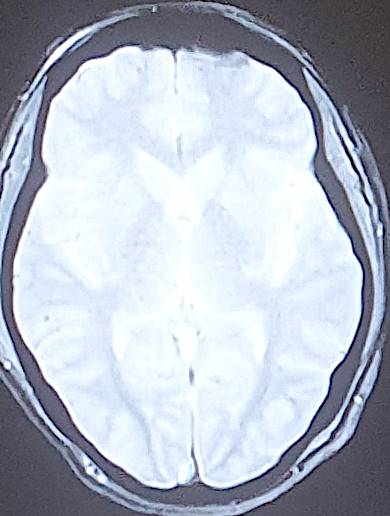

The average consultation time was 24.3 ± 14.4 hours, with extremes of 7 hours and 44 hours. Clinical presentations were headache (88.2%), visual disturbance (64.7%), disturbed consciousness (35.3%), epileptic seizures (23.5%) and motor deficit (29.4%) (Table 2). Mean systolic blood pressure was 190 ± 5.7 mmHg (extremes 150 - 24 mmHg), mean diastolic blood pressure 110 ± 5.1 mmHg (extremes 80 - 160 mmHg). Neuroradiological lesions (Figure 1) were edematous (88.2%), hemorrhagic (23.5%) and ischemic (11.7%). The topography of cerebral lesions was occipital (100%), parietal (82.3%), frontal (58.8%), temporal (47%), cerebellar (29.4%) and basal ganglia (23.5%) (Table 3).

Figure 1. Breakdown of cases by neuroradiological lesions.

Our findings on lesion topography (Figure 2 and Figure 3) are similar to those in the literature, which report that the parieto-occipital, frontal and temporal regions are most involved. More rarely, lesions may extend to the basal ganglia (14%), brain stem (13%) and splenium of the corpus callosum (10%) (Leroux et al., 2008). A normal CT scan does not exclude the diagnosis of PRES (Poma et al., 2014). Intracerebral hemorrhage is observed in 5% - 30% of PRES cases (Aracki-Trenkić et al., 2016; McKinney et al., 2012).

Figure 2. Bilateral occipital vasogenic edema.

Figure 3. Bilateral frontal-parietal-occipital edema with left lenticular hemorrhage.